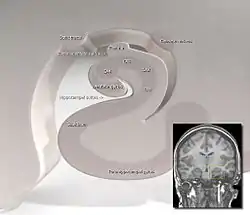

| .jpg.webp) Subiculum labeled at center left. | |

|  Subiculum to CA1 transition Artist Don Cooper and Leah Leverich | |